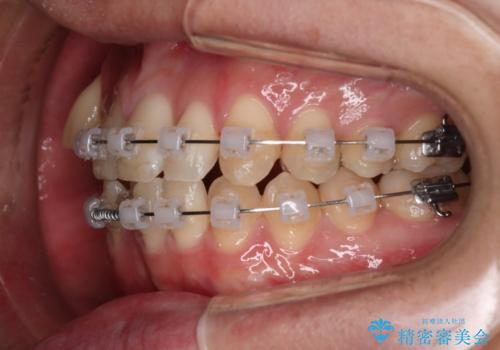

歯の移動にオープンコイルとMI(歯肉に埋入するネジ)を用いました。

非抜歯矯正だったこともあり、1年半以内という短い期間で矯正を終了することができました。